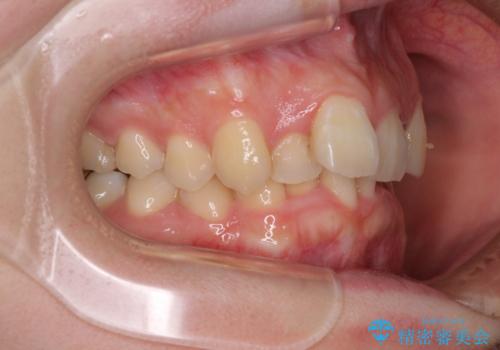

- 前歯のデコボコを気にして来院された患者様です。

上下の前歯にデコボコがあり、更にはディープバイトにより下顎前歯の大半が隠れている状態でした。

上顎左右第一小臼歯の2本を抜歯し、ワイヤー装置を使用して咬み合わせ高さを改善しながら、歯列を整えて行くこととしました。